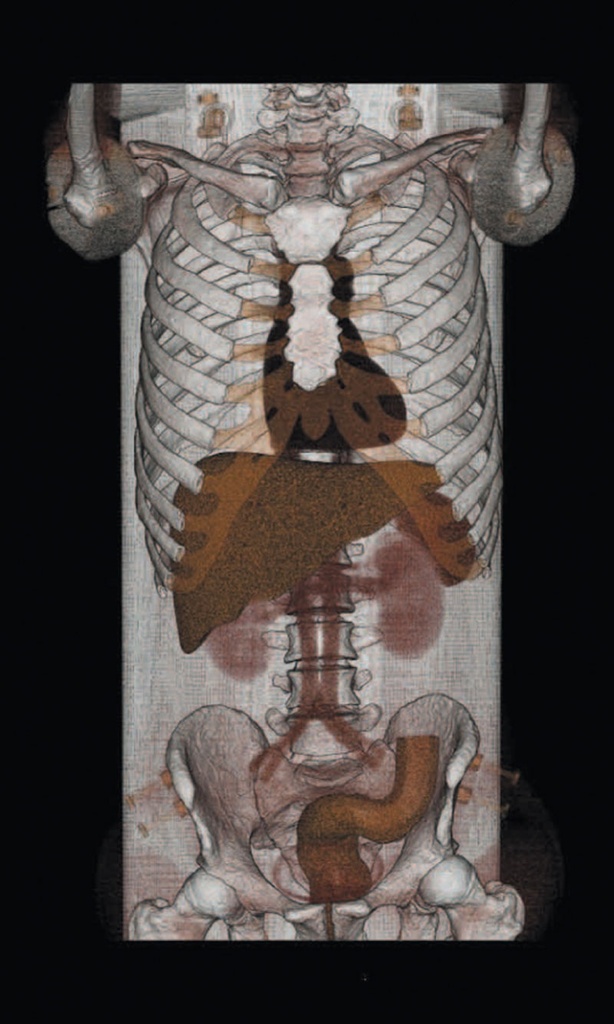

Ein einzigartiges Ganzkörperphantom für CT bietet eine Vielzahl von Ausbildungs- und Forschungsmöglichkeiten. Das Phantom kann auch für normales Röntgen benutzt werden und gibt lebensnahe Bilder. Es benden sich keine Metallteile oder Flüssigkeiten im Phantom. Die wichtigen Gelenke haben eine menschenähnliche Beweglichkeit und erlauben vielfältige Positionen für die Übung. Das Phantom kann in 10 Teile zerlegt werden. Die verbesserten Schultergelenke erlauben es, die Arme nach oben zu bewegen. Die künstlichen Organe sind anatomisch korrekt und haben entsprechende HU-Zahlen.

Innere Organe und Strukturen:

- Kopf und Rumpf

- Synthetischer Schädel

- Wirbel

- Schlüsselbeine

- Rippe

- Brustbein

- Schulterblätter

- Beckenknochen

- Oberschenkel

- Lungen mit Pulmonalgefäßen

- Leber mit Pfortader und Lebervene

- Bauchspeicheldrüse

- Nieren

- Gallenblase

- Milz

- Aorta

- Vena Cava

Radiologische Absorption und Hounsfield-Nummer ähnlich dem menschlichen Körper.